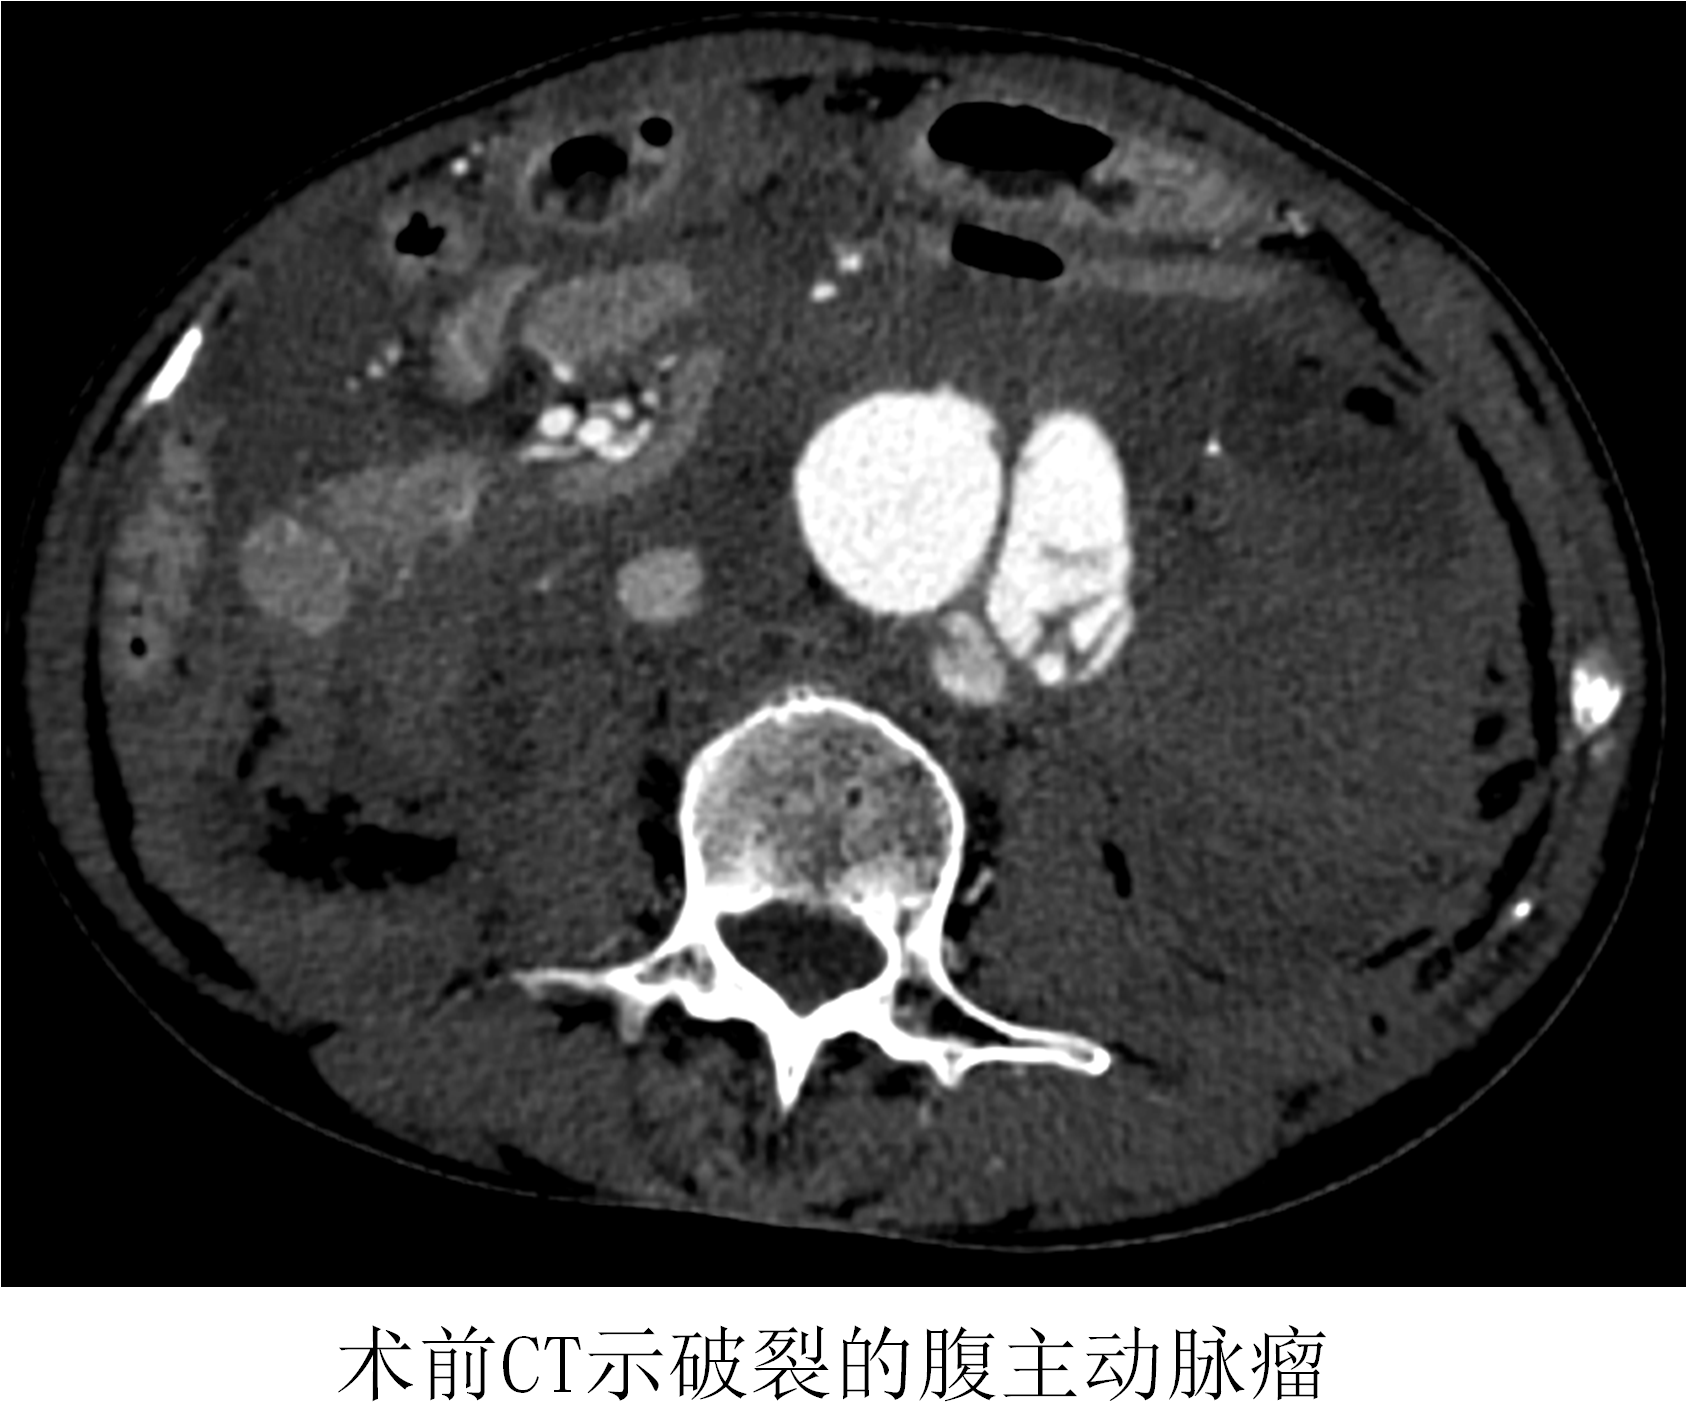

時(shí)間就是生命!在來(lái)不及全麻的情況下,薛冠華當(dāng)機(jī)立斷,局麻手術(shù)。手術(shù)由薛冠華主刀、倪其泓和王預(yù)立醫(yī)師共同協(xié)助,在麻醉醫(yī)師黃丹、手術(shù)室護(hù)士夏悅和放射科技師馬鋆的配合下緊張進(jìn)行。薛冠華通過(guò)精準(zhǔn)定位,在避免影響內(nèi)臟血管的同時(shí),采用腔內(nèi)技術(shù)在短短30分鐘內(nèi)就將腹主動(dòng)脈瘤的破口通過(guò)覆膜支架封堵,有效阻止了進(jìn)一步出血;颊叩难獕洪_始回升,情況逐漸平穩(wěn),手術(shù)順利完成。患者轉(zhuǎn)入重癥監(jiān)護(hù)室后意識(shí)慢慢恢復(fù),術(shù)后10天復(fù)查CT顯示破裂的腹主動(dòng)脈瘤隔絕良好,已于近期康復(fù)出院。